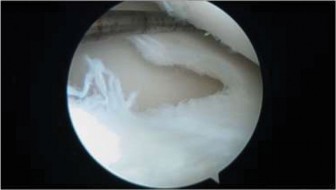

Clinical & Radiographic Imaging